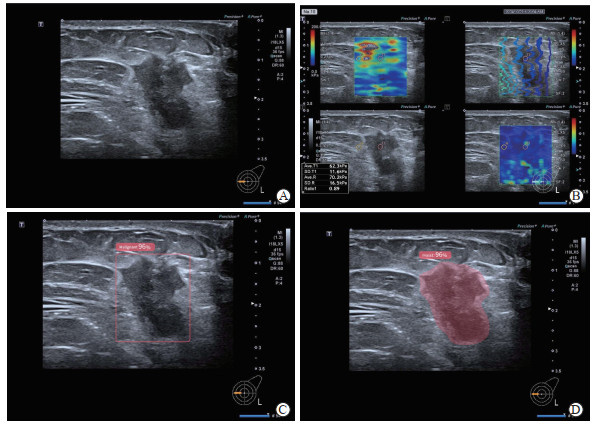

图  1  浸润性乳腺癌伴微乳头状癌的超声AI辅助诊断与剪切波弹性成像分析

A 65-year-old female patient was pathologically diagnosed with invasive breast cancer complicated with micropapillary carcinoma. A: Conventional ultrasound revealed a solid nodule at the 9 o'clock position of the left breast, presenting with a clear boundary, irregular morphology, and punctate internal hyperechoes; B: Shear wave elastography of the breast nodule showed a maximum elasticity value of 62.3 kPa; C: AI-assisted ultrasound diagnosis system identified the breast nodule, with a 96% malignant probability; D: AI-assisted ultrasound diagnosis system identified the breast nodule and performed nodule filling. AI: Artificial intelligence.

• 图  1   浸润性乳腺癌伴微乳头状癌的超声AI辅助诊断与剪切波弹性成像分析